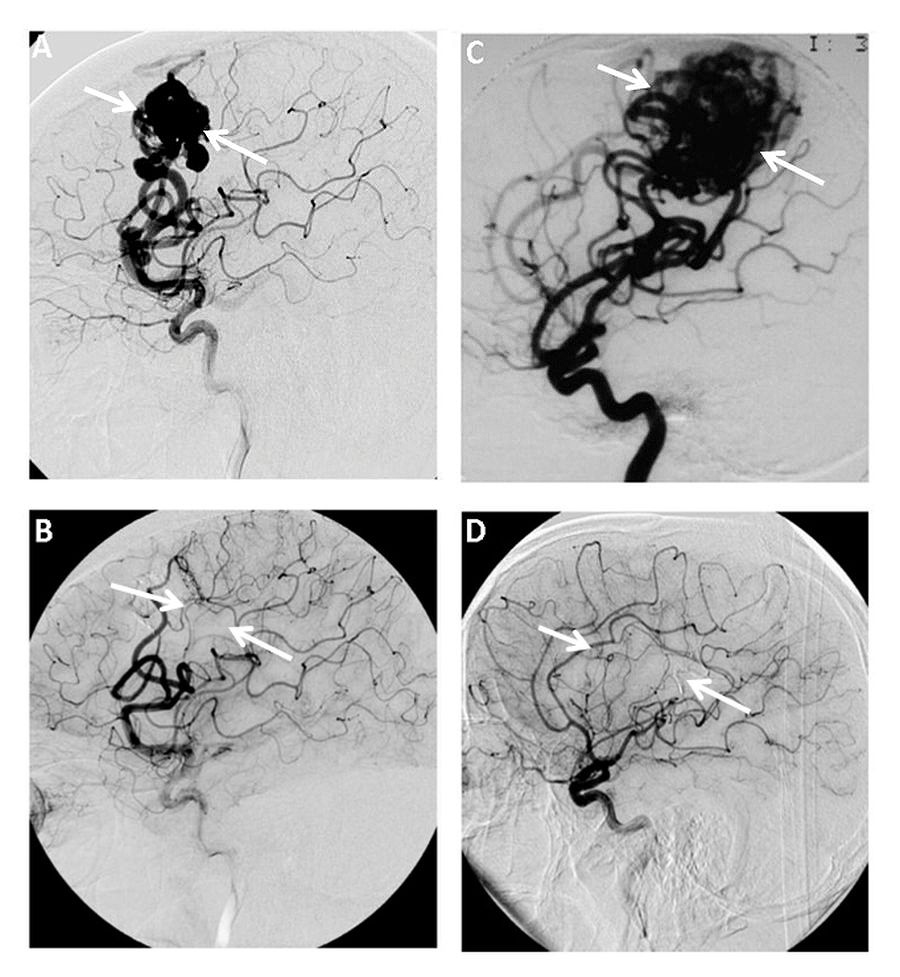

脑干动静脉畸形(AVMs)是令人生畏的病变,因为它们位于脑神经、其细胞核和关键纤维束之间不可侵犯的大脑区域之一。今天的脑干动静脉畸形可能就像20年前的脑干海绵状畸形(CMs),当时...